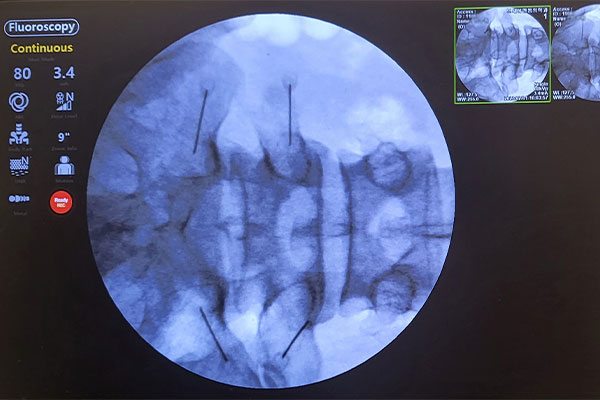

C-arm 영상증폭장치를 이용하여

신경의 상태와 신경이 지나가는

경로를 정확하게 확인합니다.